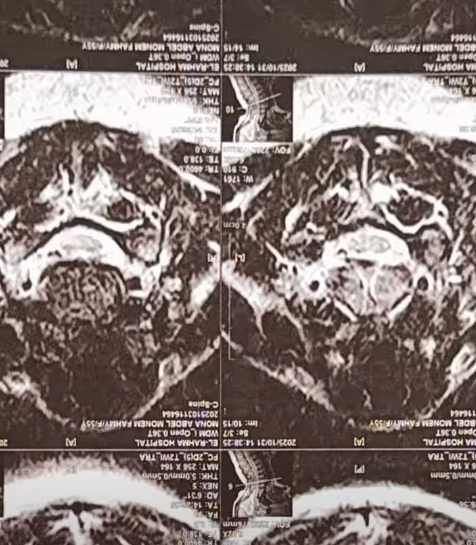

كشفت الإعلامية منى عراقي عن معاناتها من مرض مناعي نادر، مشيرة إلى أن الأطباء في مصر أكدوا لها أن المرض لا علاج له، وأنها ستضطر للعيش على العلاج الهرموني مدى حياتها.

وقالت منى عراقي في فيديو نشرته عبر حسابها على فيس بوك: الدكاترة في مصر قالولي جالك مرض مناعي ملوش علاج، واللي هنقدر نعمله إننا نكتبلك علاج هرمون هتعيشي بيه باقية حياتك.

وأضافت منى عراقي: قعدت 3 سنين أجرب كل حاجة علشان أخف، لحد ما قابلت سيدة ألمانية كانت مصابة بنفس المرض، وقالتلي علجي السبب الأساسي للمرض مش الأعراض.